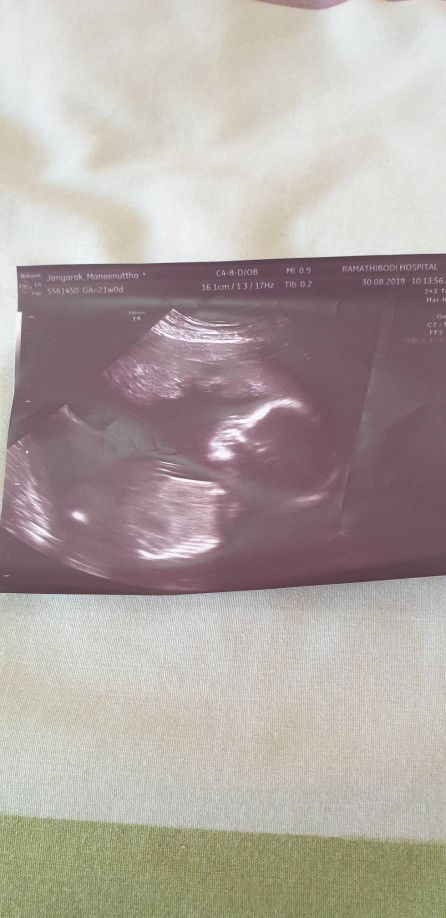

สวัสดีค่ะ มาอวดรูปลูกกันว่าตอนนี้กี่เดือนแล้ว บ้านไหนน้ำหนักจ้ำม้ำแบบบ้านแม่โอ๋กันบ้างค่ะ

5เดือน6วัน น้ำหนัก9โลเลยค่ะ